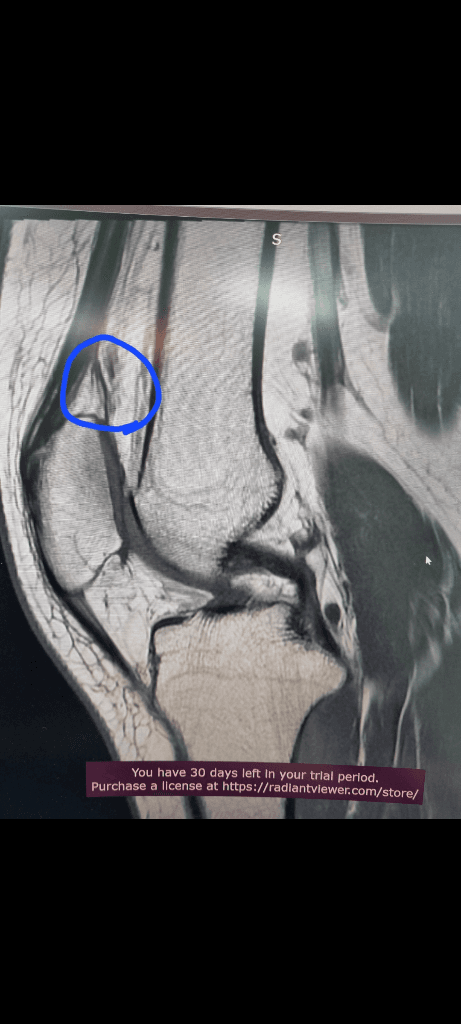

1. 추벽이 아닙니다.

2. 슬개골 관절면에 외상으로 인한 골수부종입니다.

3. 관절면 손상여부는 첨부해주신 영상만으로 알 수 없습니다